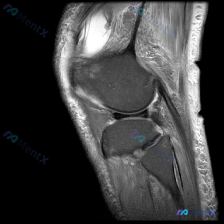

看到一个很典型的临床-影像矛盾病例,整理出来和大家分享思路。 病例核心信息 这是一张膝关节矢状位MRI单张图像,临床关注点为「半月板异常」,我们先来看影像的全面评估结果: 1. 骨骼结构:股骨远端、胫骨近端、髌骨轮廓完整,无明显骨皮质中断或骨折 2. 关节软骨:股骨、胫骨关节面软骨信号均匀,无明显剥...